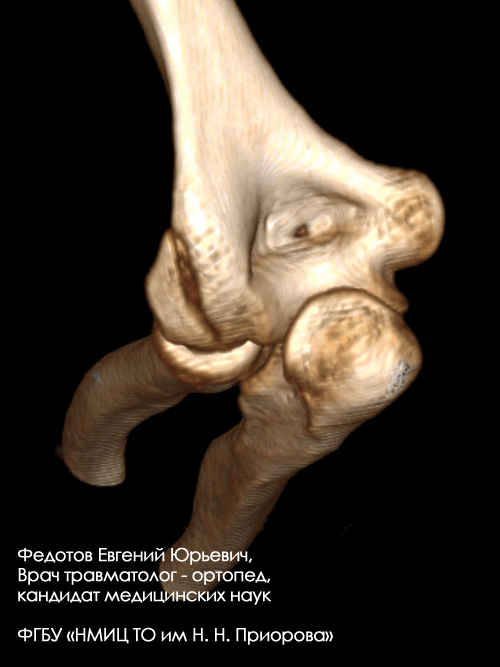

Пациентка с тяжелым внутрисуставным переломом нижнего отдела (мыщелков) плечевой кости с тяжелым повреждением локтевого сустава.

Рентгенограмма до операции.

Выполнена операция: металлоостеосинтез плечевой кости современными пластинами LCP, анатомия локтевого сустава полностью восстановлена.

Гипсовая повязка после операции не применялась, сразу разрешена разработка движений в суставах конечности. Результат через 5 дней после операции. Швы еще не сняты, виден отек, кровоподтеки на конечности после перелома. Уже видна хорошая функция конечности.

Результат через 3 мес. после операции. Функция конечности полностью восстановлена.

Пациентка с тяжелым внутрисуставным переломом нижнего отдела (мыщелков) плечевой кости с повреждением локтевого сустава.

Выполнена операция: металлоостеосинтез плечевой кости пластинами LCP, анатомия локтевого сустава полностью восстановлена. Гипсовая повязка после операции не применялась, сразу разрешена разработка движений в суставах конечности.

Результат через 14 дней после операции. Швы только что сняты. Уже видна функция конечности, достаточная для обслуживания себя в быту.

Пациентка с чрезвычайно тяжелым повреждением: тяжелым внутрисуставным переломом нижнего отдела плечевой кости с повреждением локтевого сустава с перелом средней трети локтевой кости со смещением отломков (дорожная травма).

Выполнена операция: металлоостеосинтез плечевой кости пластинами LCP, анатомия локтевого сустава полностью восстановлена, остеосинтез локтевой кости стержнем с блокированием через небольшие разрезы-проколы (до 1 см.).

Гипсовая повязка после операции не применялась, сразу разрешена разработка движений в суставах конечности. Результат через 3 недели после операции. Уже видна хорошая функция конечности.

Результат через 4 мес. после операции. Функция конечности полностью восстановлена. Конечность ничем не отличается от здоровой.